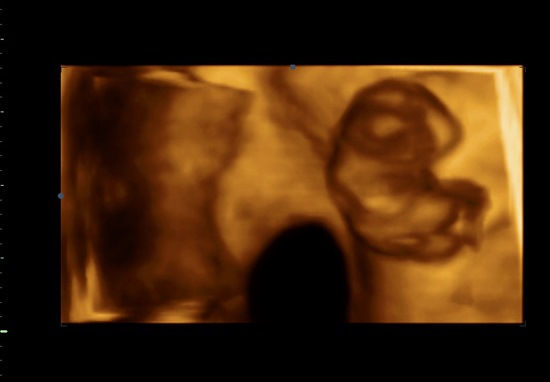

УЗИ на девятой неделе беременности

Девятая неделя беременности: развитие эмбриона

Эмбрион в 9 недель уже достигает 20-30 мм и весит примерно 4 г. Теперь вся связь с материнским организмом происходит через уже полностью оформившуюся плаценту. У ребенка удлиняются конечности, выпрямляется позвоночник, а «хвостик» превращается в копчик. У малыша уже можно заметить крохотные ноготки, образовавшиеся в результате утолщения эпидермиса концевых фаланг пальцев.